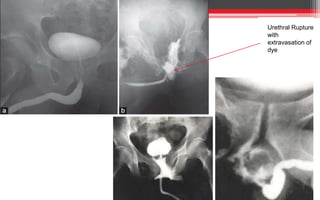

• If there is blood at the external meatus or the urine is blood-

stained, a urethrogram using water-soluble contrast material may

demonstrate the extravasation BUT may worsen the injury.

Urethral Rupture

with

extravasation of

dye